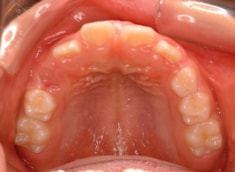

治療前